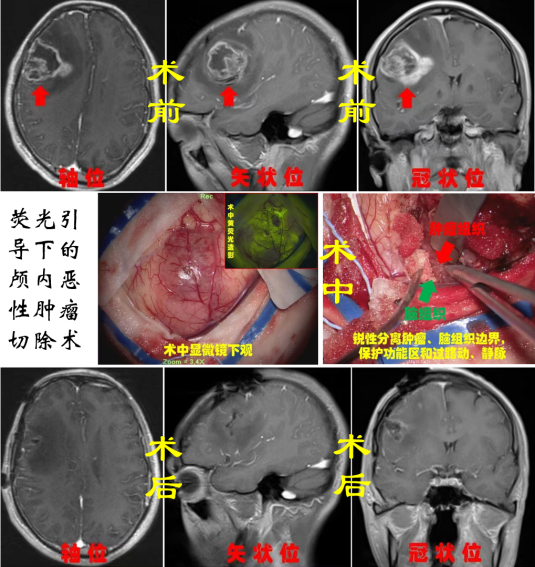

神經腫瘤:神經腫瘤作為神經系統疾病中最為棘手的疾病之一,常見的有膠質瘤、腦膜瘤、垂體瘤、神經鞘瘤、轉移瘤、先天性腫瘤等,手術方式包括超聲導航+熒光造影引導下腦腫瘤切除術、鞍結節腦膜瘤切除術等,借助顯微鏡等先進設備,在保留正常腦組織的情況下,最大程度切除腫瘤組織,為患者爭取后續康復機會。

7301b9c9b7144d69bb38c6a635a3f512.Png6efcf3a55301466dbf75113390793f2e.Png